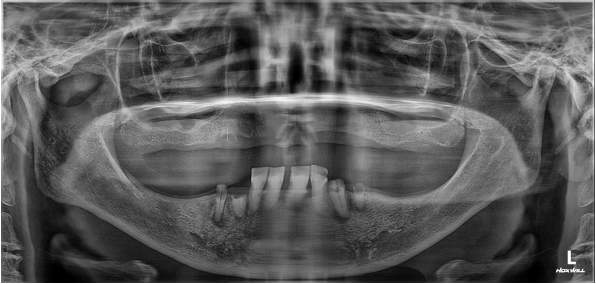

디지털 풀아치 임플란트(상악) (73세 남성)

디지털 풀아치 임플란트(상악) & 전체 임플란트(하악) (64세 여성)